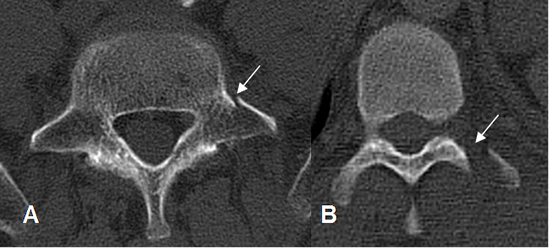

Fig 207. Fractura de apófisis transversa.

A y B: TAC axial. Fractura no desplazada de la apófisis transversa en A y desplazada en B.